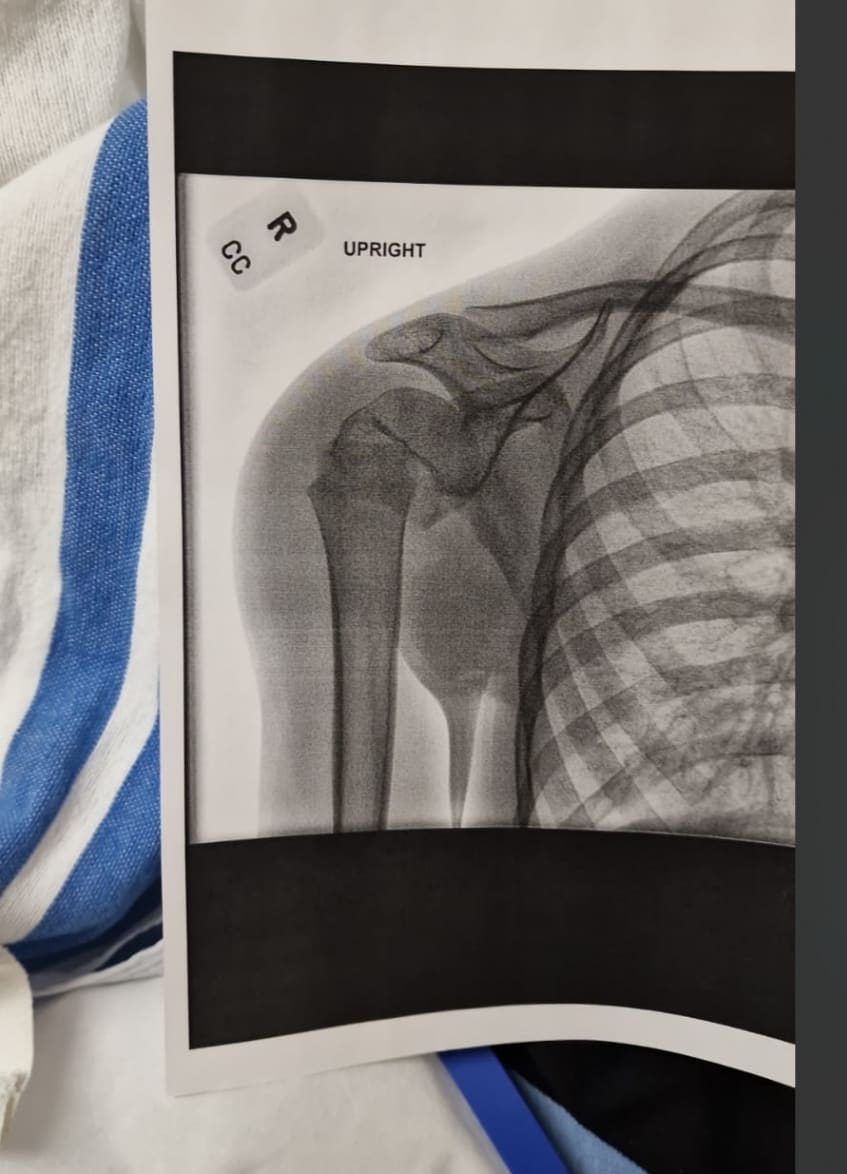

Comme cela a un peu causé du système américain, petit rapport d'il y a 48 heures. Mon gamin se fracture l'humerus en snowboard. Je l'emmène vers 14H à l'hosto après qu'il ait été pris en charge gratos par la station pour les premiers soins, me conseillant d'aller faire une radio, on ne sait jamais car il souffre un peu.

Présentation du passeport et direct en salle d'urgence. Cela m'a rappelé les épisodes du docteur House, plusieurs infirmières ou aides soigantes se succèdent, chacune avec un rôle précis, gestion de la douleur et prescription, observation des symptômes, puis manip radio qui l'emmène 5 mn. Tout ceci prend 1H. Après 10 mn, une autre infirmière revient m'informant que l'humerus est fracturé, qu'ils viennent d'appeler le chir qui décidera quoi faire. Il arrive 30mn après avec la radio me dit qu'il va l'opérer dès qu'un bloc se libère. La douleur monte chez le gaminqui pleure, et hop, oxycodone, redoutable d'efficacité en 5mn. Il est 17H,; le chir revient me disant que un bloc s'est libéré, et nouveau balai avec d'autres infirmières puis l'anesthésiste et le chir qui me détaille l'intervention. Bref, ils me le rendent à 18H30 en salle de reveil et à 20H30 on était rentrés.

Hopital nickel, matos de dingue et petit hopital de station de ski dans une ville de 20 000 habitants je pense.

Incision de 2.5 cm pour remettre en place la tête d'humerus fracturée et déplacée, suture nickel. chapeau.